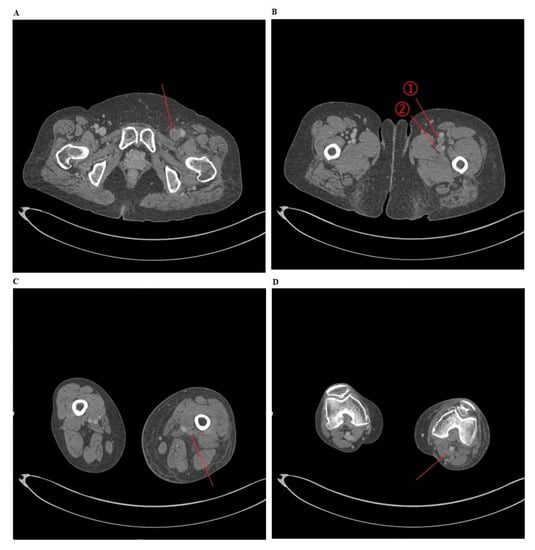

Depending on the presence of DVT on CT venography, the patients were divided into two groups: the DVT group and the non-DVT group (Figure 1). Then, baseline and clinical characteristics of the patients were compared between the two groups.

To consider the possibility of lower extremity edema arising from DVT, a CT venography was performed for (A) the common femoral vein, (B) ① the superficial femoral vein ② the deep femoral vein, (C) the popliteal vein, and (D) the popliteal vein.

Figure 1. Deep vein thrombosis (DVT) on computed tomography (CT) venography.